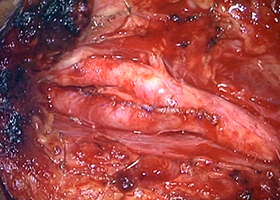

② 頚動脈狭窄症

脳梗塞の原因となる頚動脈狭窄症に対して内膜剥離術を行います。

56歳男性、左半身麻痺で発症しました。

[術前画像所見]

右側で頸部内頚動脈が細くなっているため右脳に脳梗塞を生じた患者様です。

[手術所見]

手術で血管の内部で肥厚した内膜を除去します(内膜剥離術)。

-

右頚動脈の露出 -

内部に充満したプラーク -

プラーク除去 -

血管壁縫合

[術後画像所見]

術後造影CT -

術後MRI拡散強調画像

頸部狭窄は解消しており、新たな脳梗塞など生じていません。